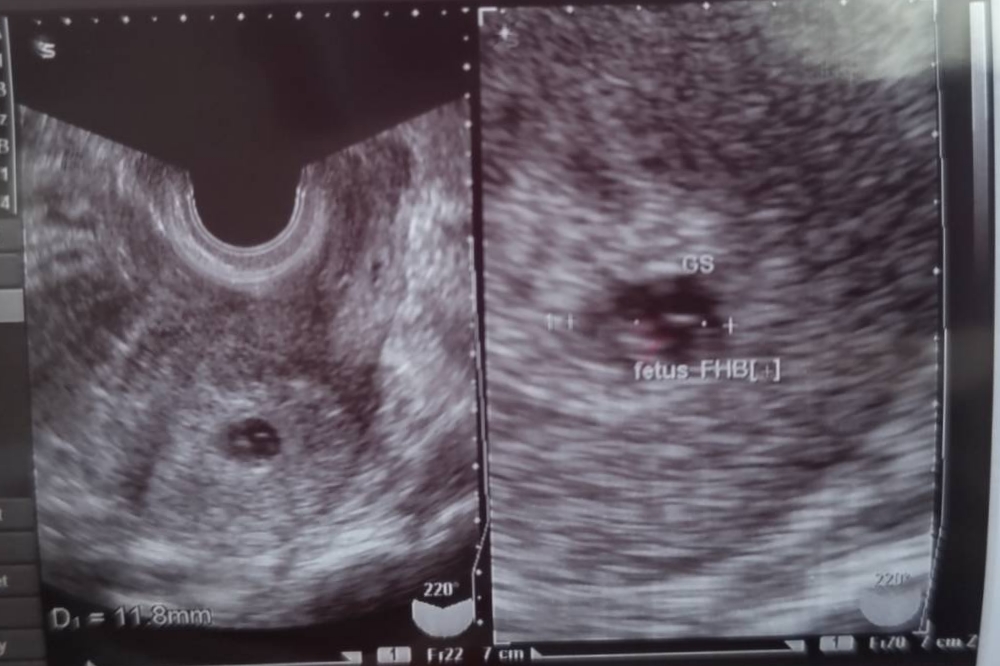

この度妻が新しい命を授かりしました👩🍼 約6週になります、安定期までは油断できませんが見守りたいと思います😊…